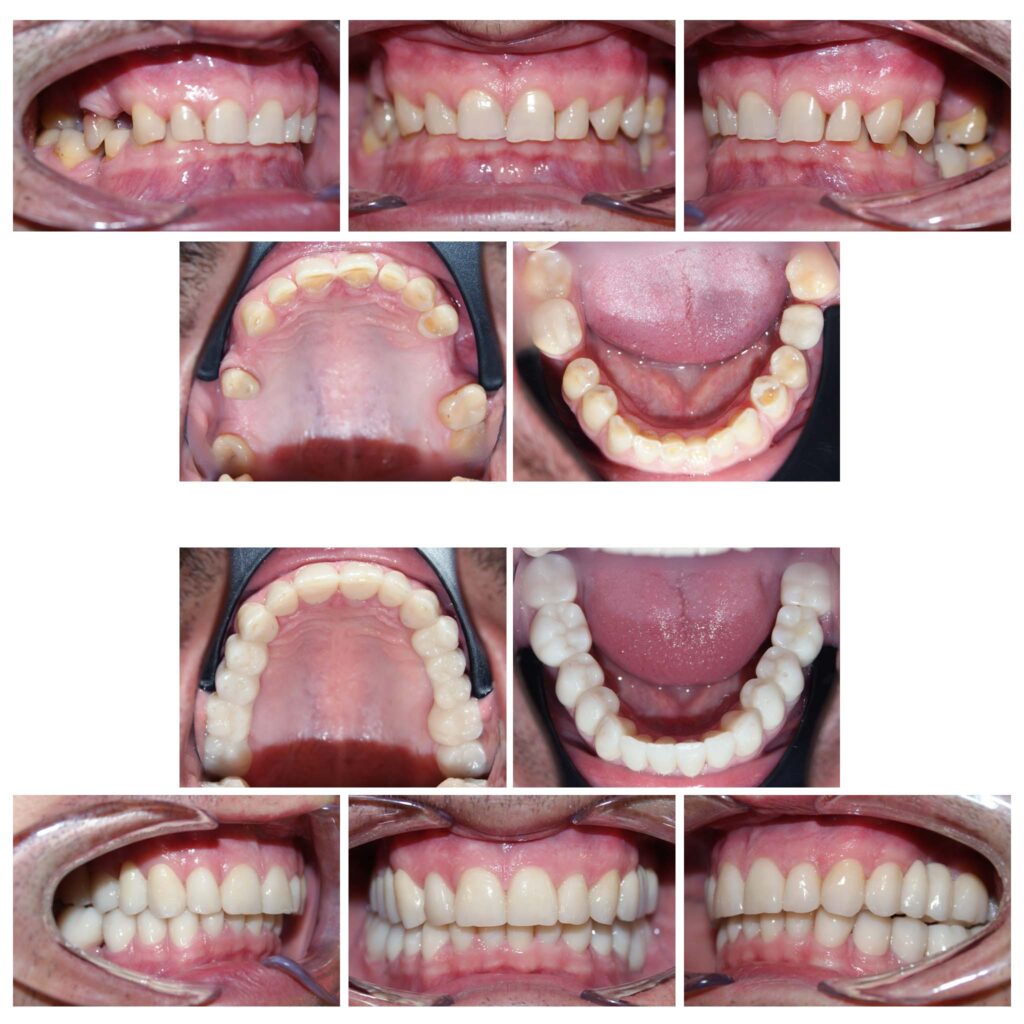

Reabilitare complexă și completă a dinților cu un accent grav de uzură, a dimensiunii verticale de ocluzie și a zâmbetului = restabilirea tuturor funcțiilor naturale